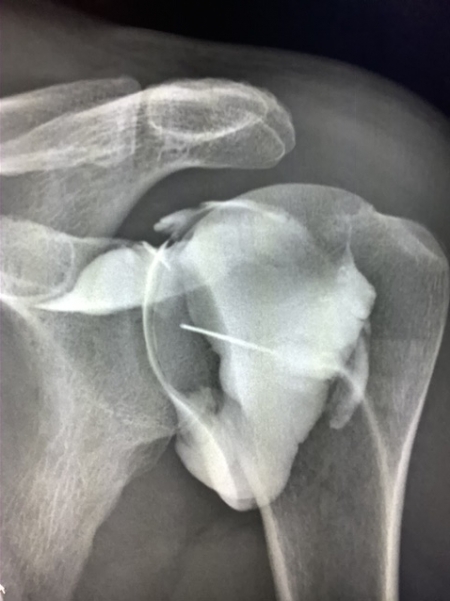

Shoulder X Ray Image . The shoulder series is fundamentally composed of two orthogonal views of the glenohumeral joint including the entire scapula. Provides better detail of cortical and trabecular bone structures than mri at cost of higher radiation exposure. Understand mechanisms of injury and the likely fractures/dislocations which may. Additionally, the image can provide information on the position of the shoulder joint, any bone. The shoulder ap view is a standard projection that makes up the two view shoulder series. Understand what injuries will be demonstrated on different projections. There for optimal for visualization of bony defects. The projection demonstrates the shoulder in its natural anatomical position allowing for adequate radiographic.